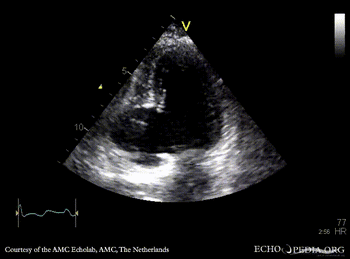

| A2CH: aneurysm of basal inferior wall | A2CH: Color Doppler |

| A4CH: aneurysm of basal inferior wall | |